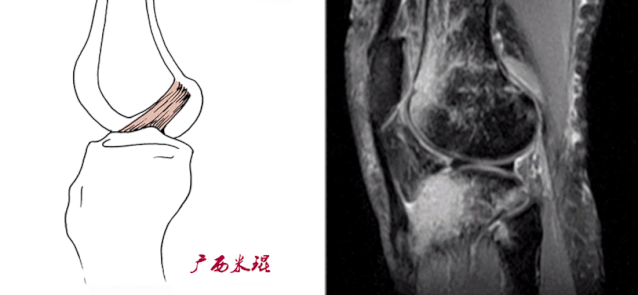

(二)ACL的正常MRI表现

各序列均为低信号。

韧带平直,边界清楚,有较好的张力。

韧带内可有脂肪及滑膜条纹影。

(四)ACL最好的观察层面

最好的观察层面是斜矢状面。

必须结合横断面和冠状面。

(五)ACL角度

矢状面ACL与髁间窝的顶部形成一个13°的夹角。